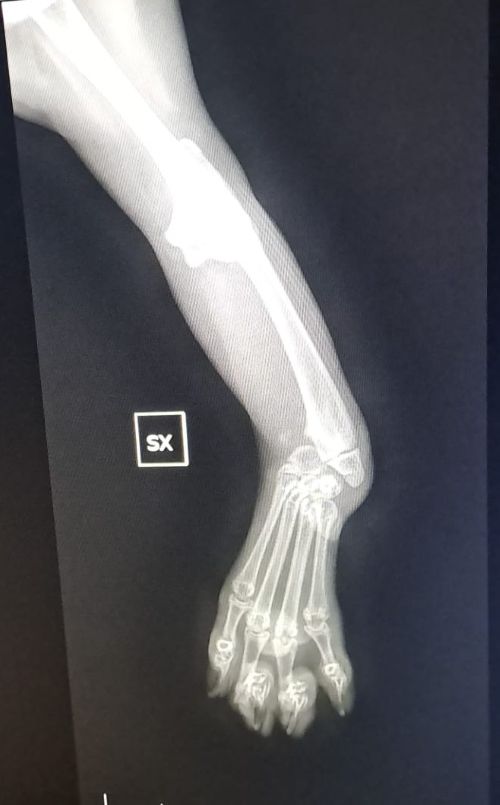

Denn inzwischen wurde Pino auf Sardinien untersucht und geröntgt. Es war sehr stark zu erwarten, dass es sich um eine angeborene Anomalie handelt. Und dies ist auch so. Pinos „Ellenknochen“ (Radius) fehlen auf der einen Seite ganz, auf der anderen Seite ist er unterentwickelt. Das führt dazu das seine Füßchen mit den Ellenbogen nicht stabil verwachsen sind und die Gelenke nicht festsitzen. Dadurch wachsen auch die Knochen nicht entsprechend und haben krankhafte Veränderungen.

Der kleine Mann ist eine „Känguru-Katze“, seine verkürzten Vorderbeine wird er nie richtig belasten können, so wie es im Moment aussieht. Ein normales Katzenleben in Freiheit ist für ihn unmöglich. Gott sei Dank zeigen sich aber keine andere Anomalien in seiner Anatomie.